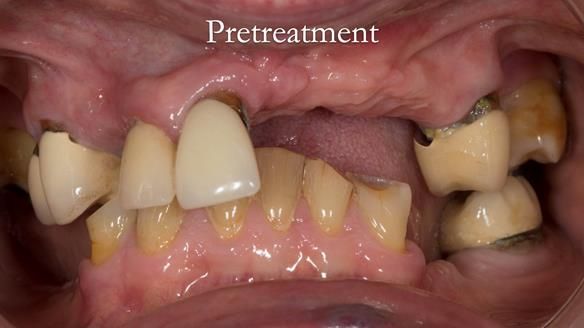

Aesthetically and functionally poor RPDs were replaced for Eileen, a 74 year old woman.

Referred to me by her general dental practitioner specifically for replacement RPDs.

Dental concerns

“Top denture loose making conversation difficult at times. Also, appearance isn’t good. Teeth uneven”

Diagnoses

- Missing teeth in the upper and lower jaws

- Upper and lower metal based RPDs, poorly fitting, worn occlusal surface, reverse curve aesthetics, lacking support

- Poor dental appearance with reverse incisal curve

- The upper right central and lateral incisors with post crowns. Healthy and functionally secure but with poor appearance, contributing to the reverse curve.

- Moderate to heavily restored dentition with deep overbite (Class 2 div II)

- Yellowish lower front teeth with small amount of wear.

- The lower right canine (LR3) is worn with MOD cavity.